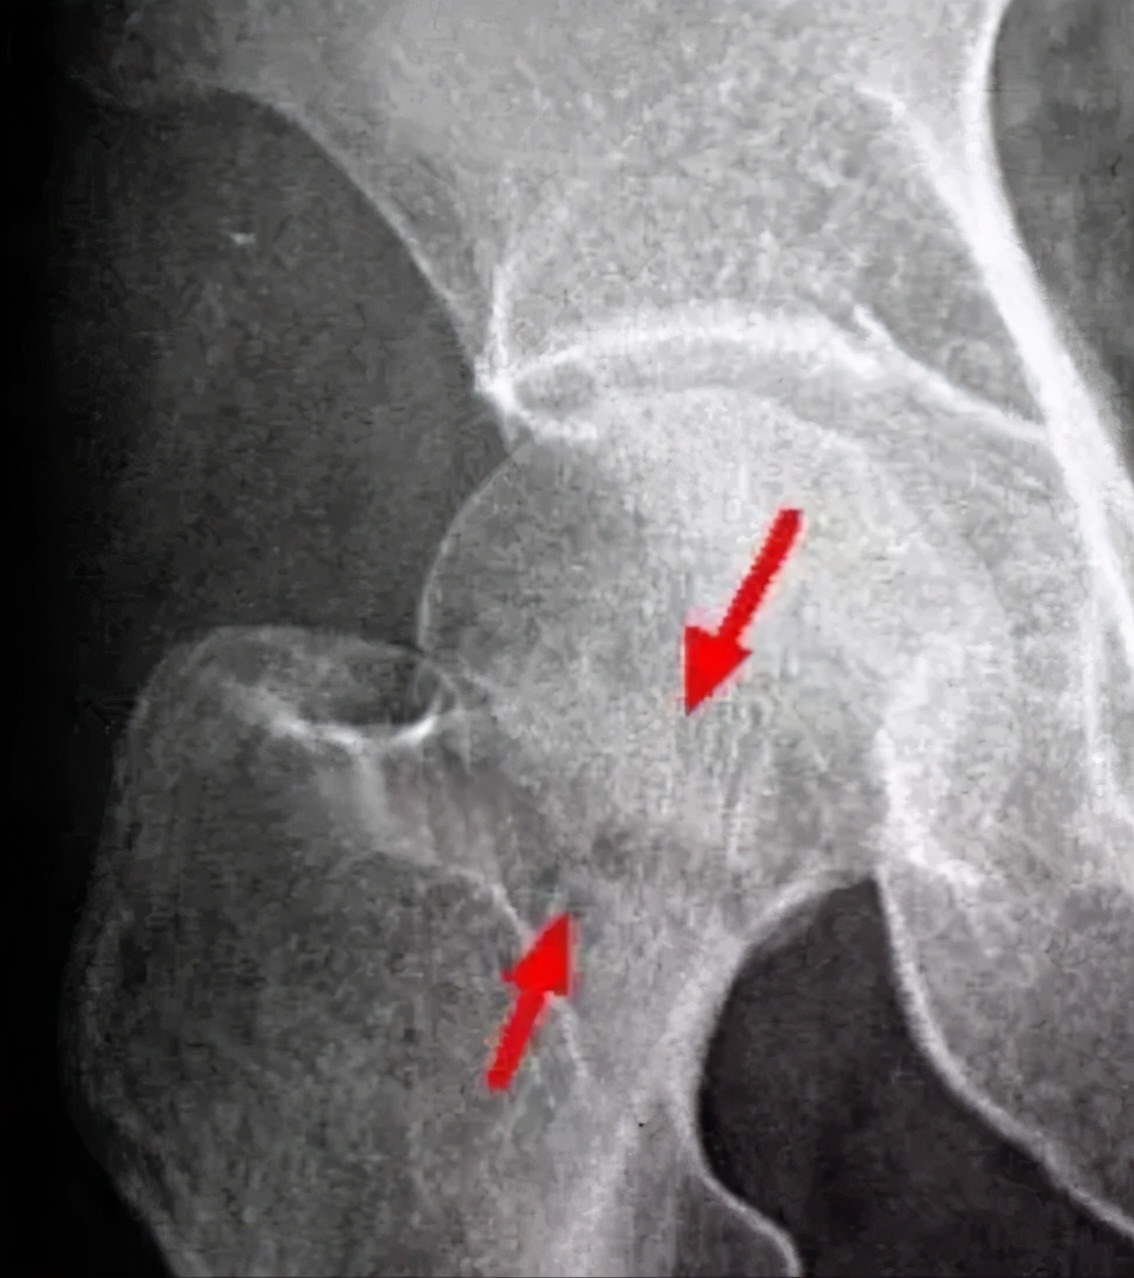

治疗后:股骨头光滑圆润,外形修复,骨密度均匀,骨小梁重新排列。